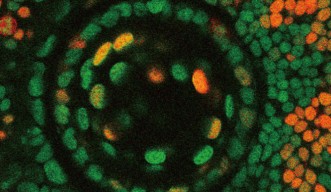

A mutated eye offers a glimpse of a key protein for preventing cancer

Researchers have showcased the central role of a specific protein for stopping cell death and regulating the cell cycle.